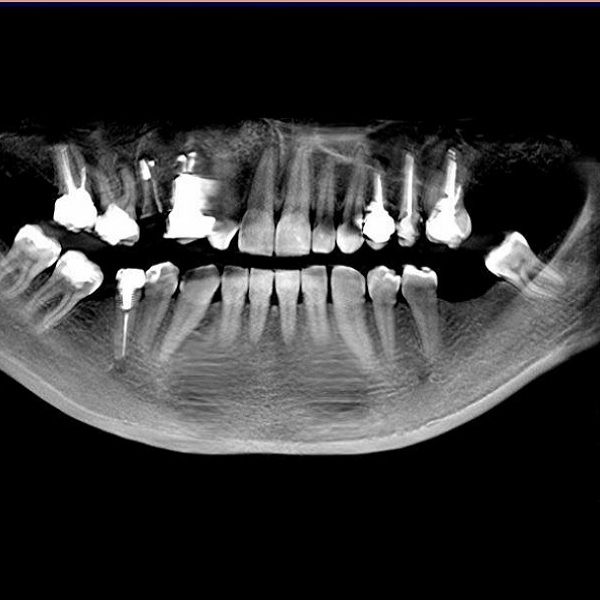

Такое исследование позволяет определить проблемы не только 2−3 соседних зубов, но и диагностировать состояние всей зубочелюстной системы и прилегающих структур, выявить на ранней стадии кисты, гранулемы, опухоли. Благодаря возможностям панорамного снимка удается более четко определить пораженный зуб, обнаружить различные аномалии развития, уточнить оптимальное место для вживления импланта, максимально качественным образом провести ортодонтическое и пародонтологическое лечение.

Несмотря на то, что прицельный снимок зубов по-прежнему широко используется в стоматологии, все более значимую роль играют и другие виды диагностики. Чтобы добиться максимально качественного результата лечения зубов, специалисты клиники Совершенная улыбка активно обращаются к ортопантомограмме

Панорамный снимок становится все более востребованным в качестве скрининговой методики. Высокая скорость проведения исследования, использование современного оборудования позволяют считать такой вид диагностики абсолютно безопасным. Она может проводиться по мере необходимости, несколько раз в году.